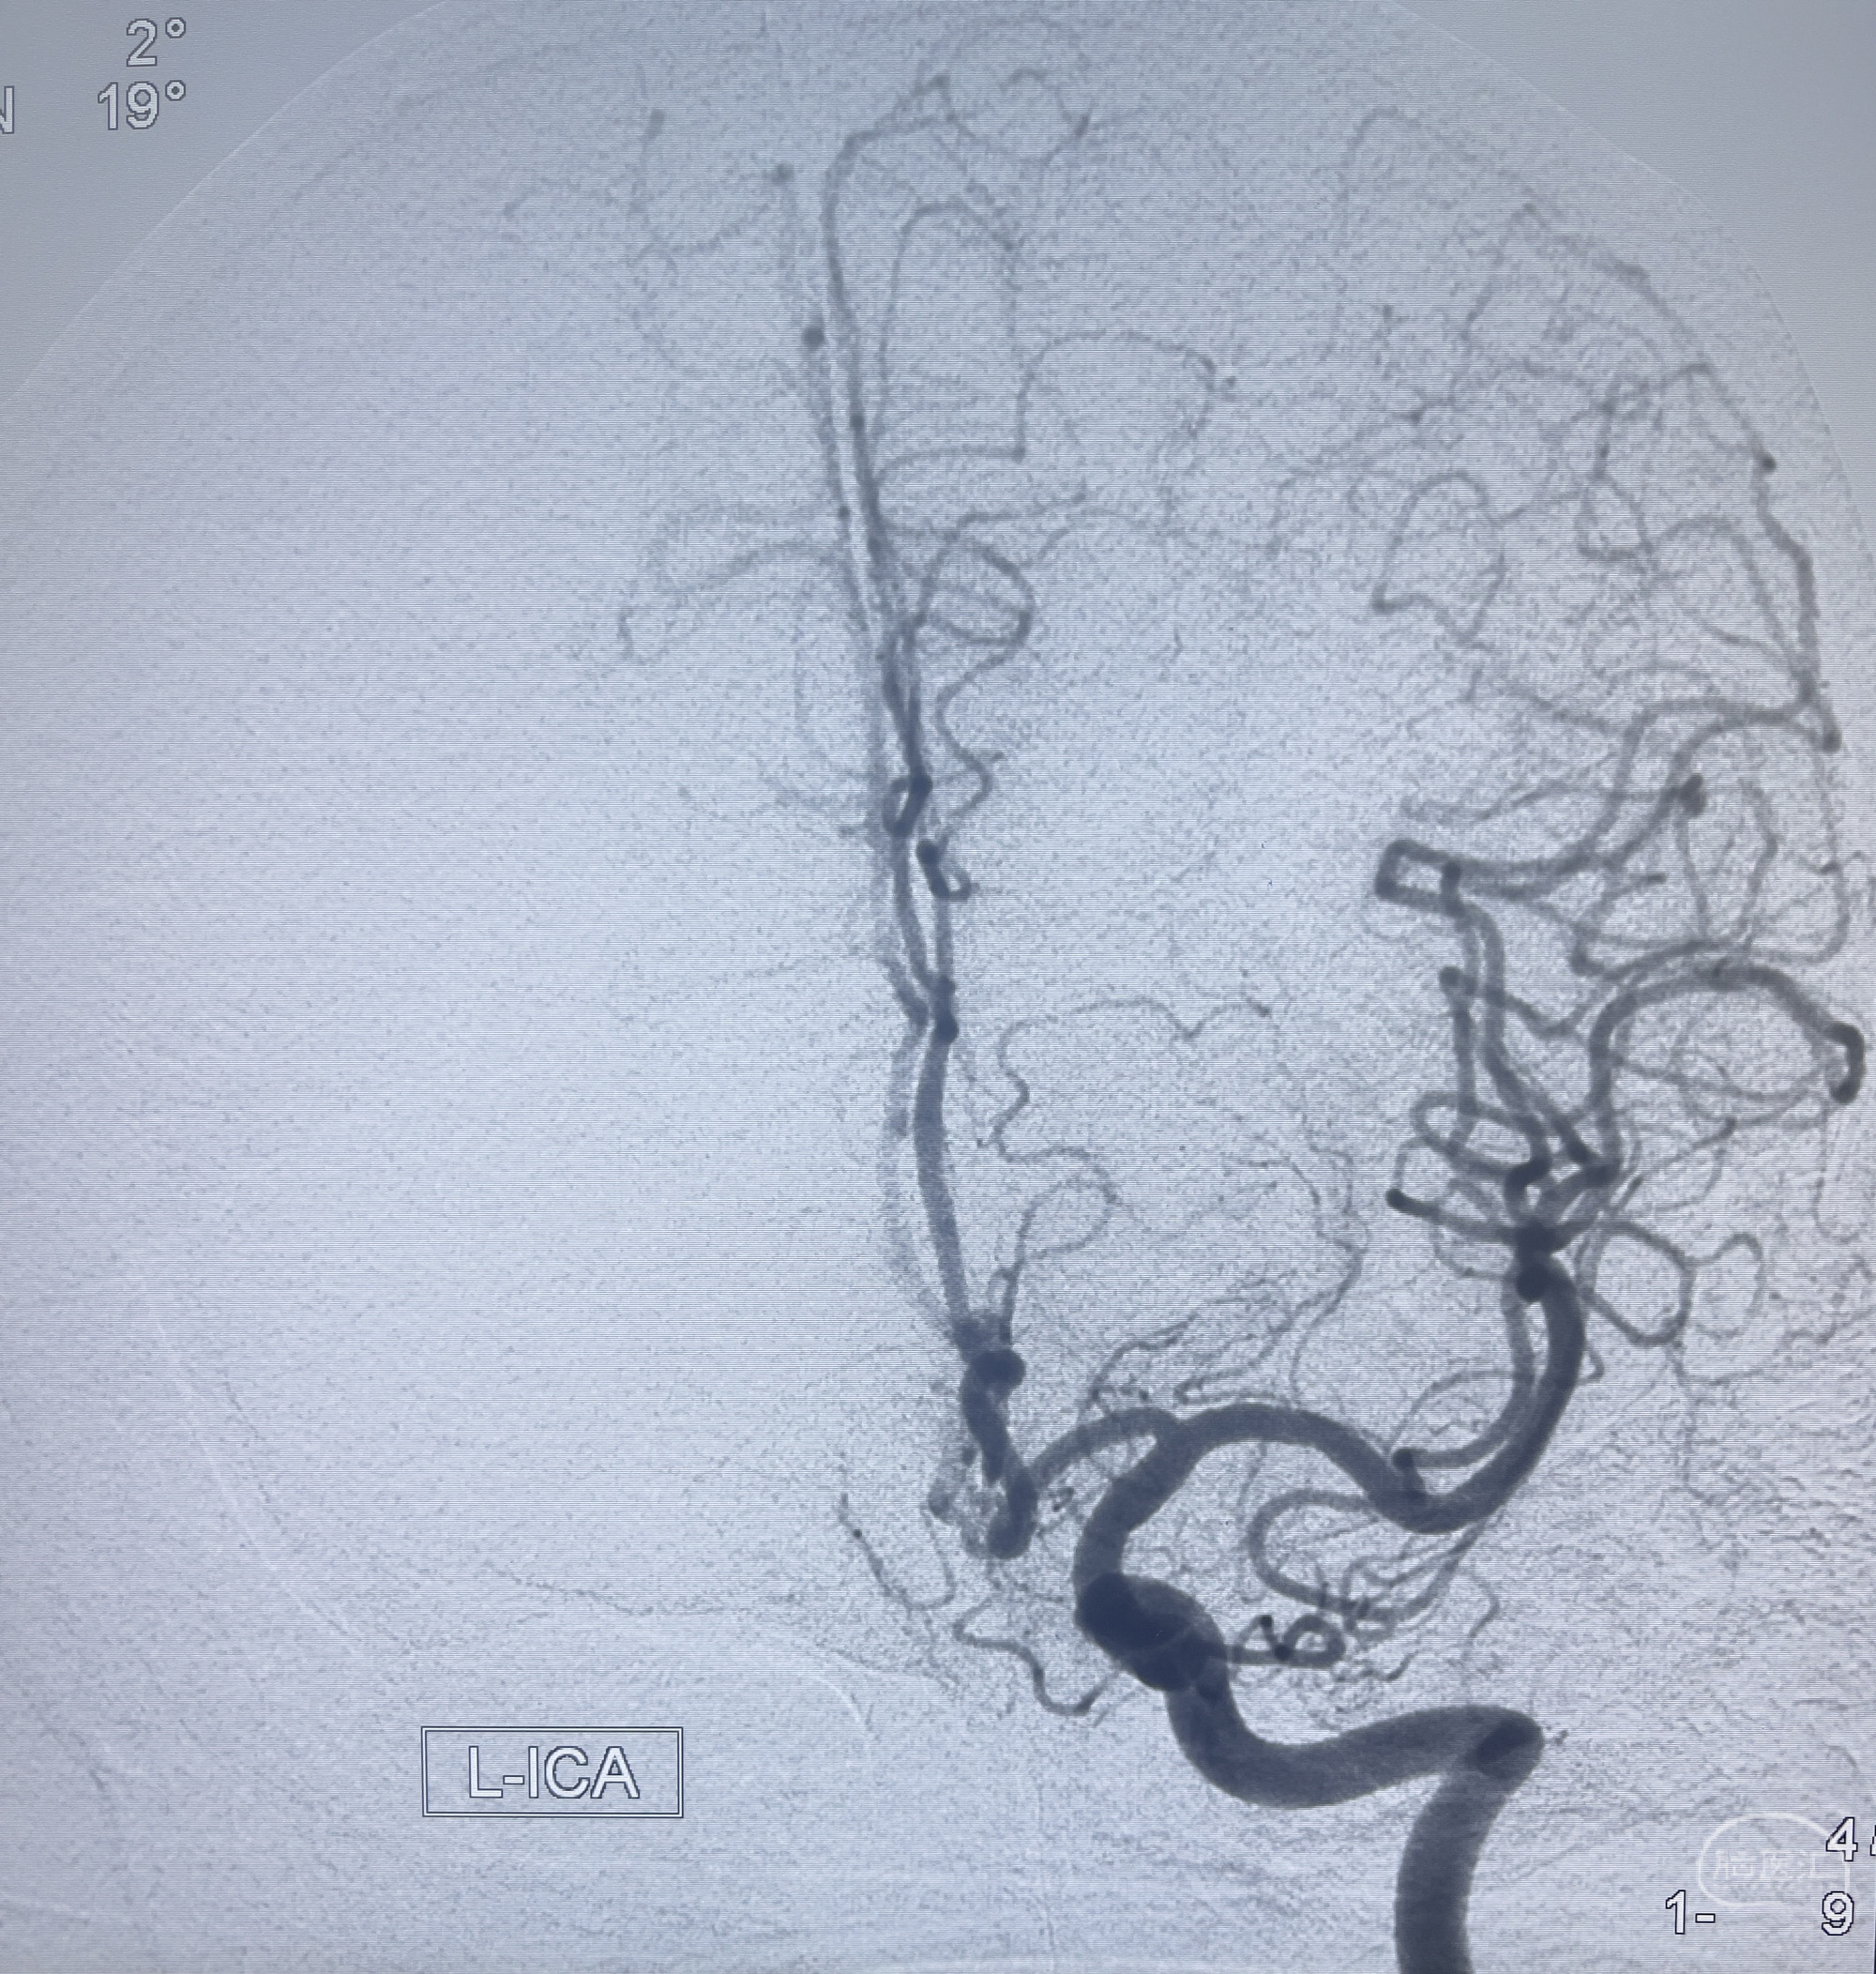

202.04.28脑血管造影:右侧大脑后动脉远段闭塞,右侧椎动脉V4段可见“囊状造影剂填充影”,大小7.64*7.65mm,可见PICA由动脉瘤发出;

1.普通支架辅助弹簧圈栓塞?

2.密网支架辅助弹簧圈栓塞?